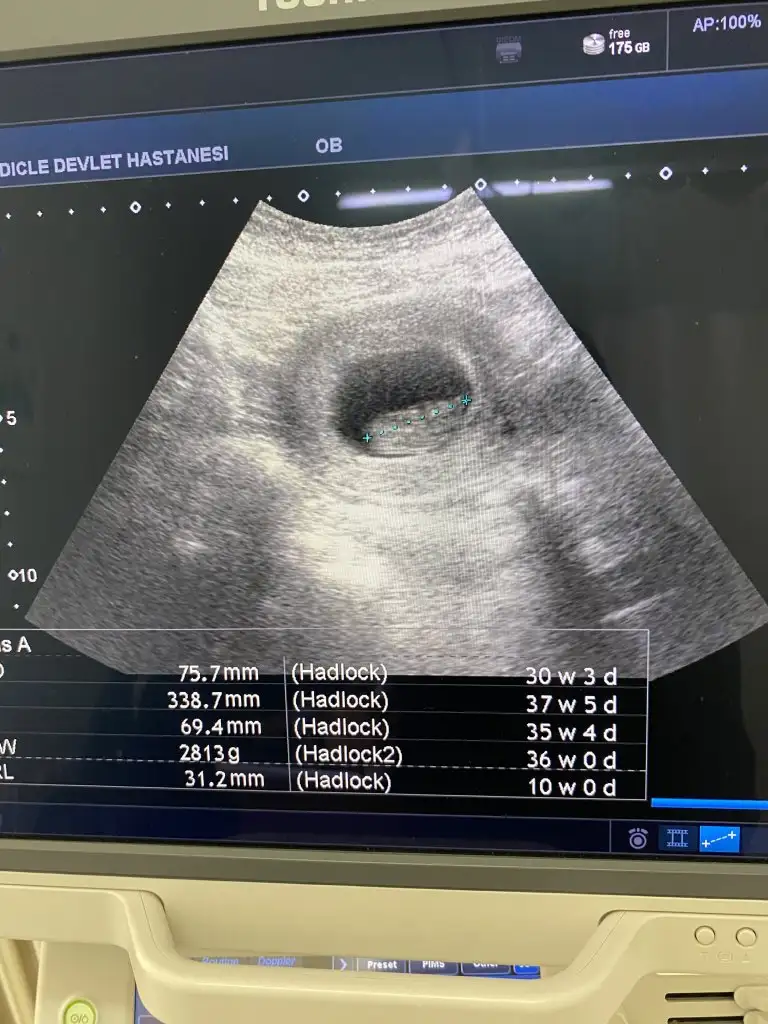

İşte fetal dna diğer tarama testlerinden bir tık üstü ama tamam temiz çıktı her şey yolunda gibi bir şey olmuyor maalesef. Dilerim sorunsuz olur da süreç verdiğiniz para olsunBenim doktorum perinatolog kendisi önerdi bu testi hatta şu şekilde söyledi ikili üçlü dörtlü artık gereksiz biz her ultrasonda inceliyoruz gereğini zaten oyuzden onları artık yapmıyoruz fetal dna en sağlıklısı dedi